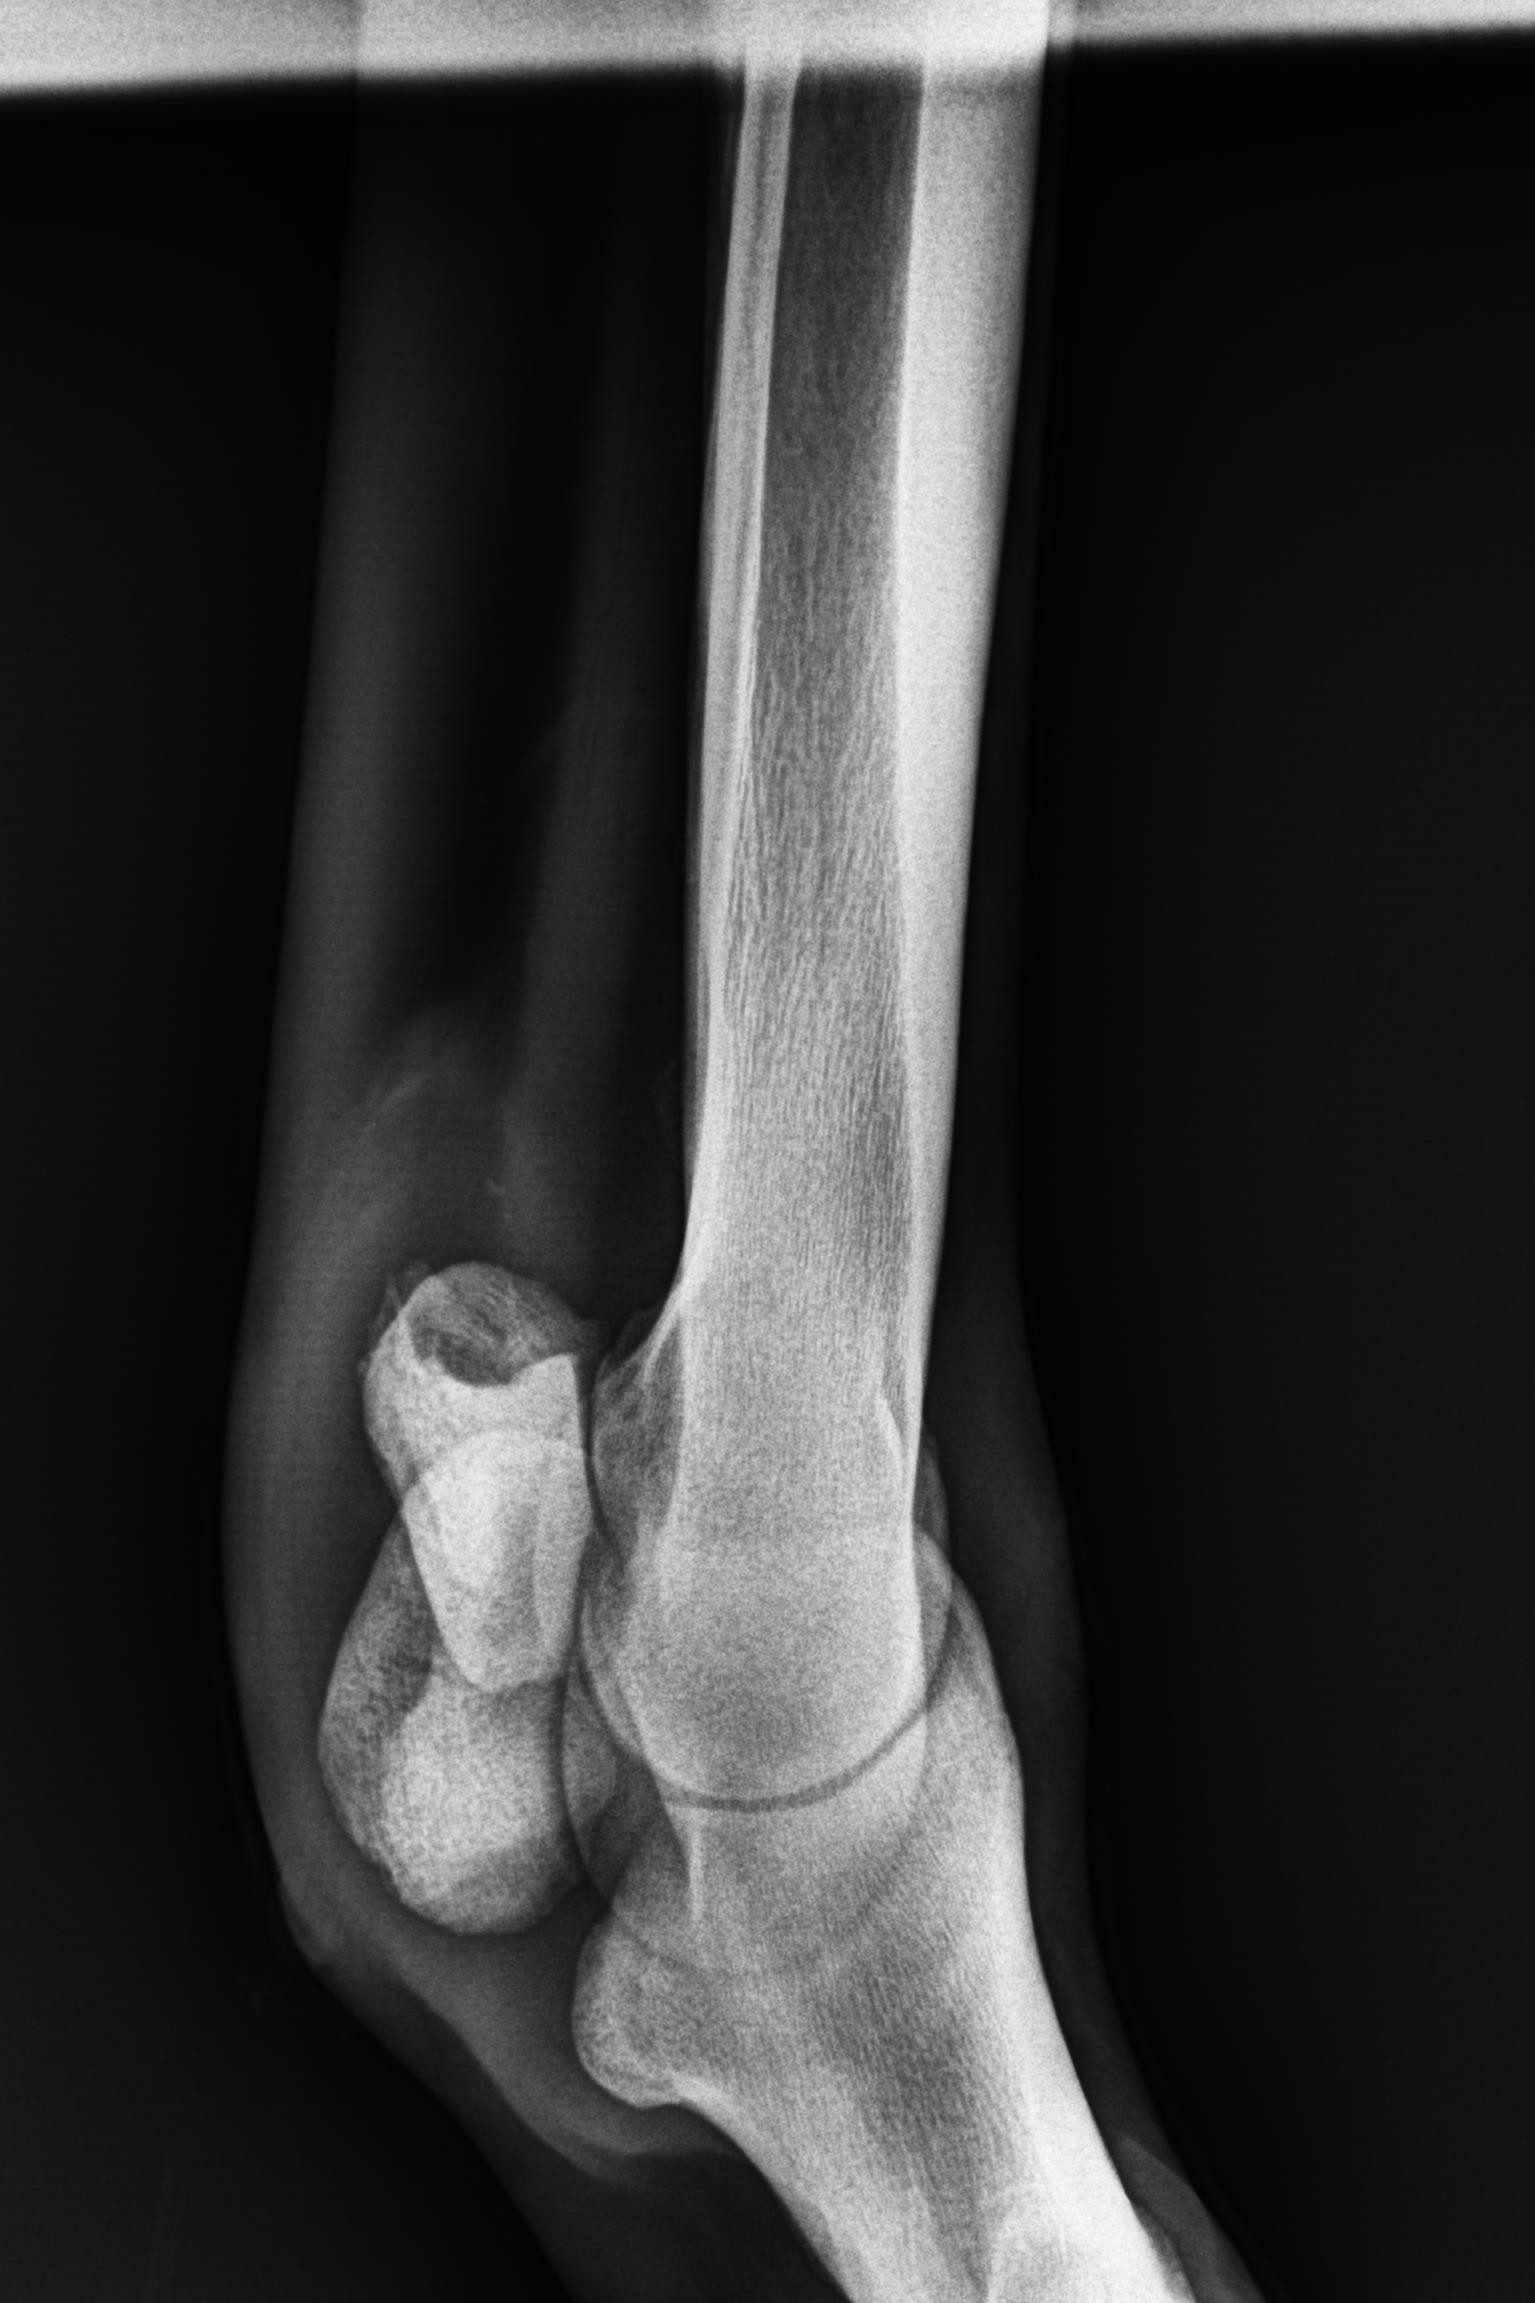

そんな状況の中、1月9日にレントゲン検査を受けると「左前肢外側の種子骨のボーンシスト」が原因と判明しましたので、サラブレッドオークションへ出品とさせていただきます。現状のままでは競走馬としてのデビューは難しいかも知れません。皆様には現状をご理解いただき、事前に獣医検査を受ける等、ご納得をいただいた上でのご検討、ご入札をお願いし、現状渡しのノークレーム、ノーリターンでお願いいたします。

セールの後からお預かりして来ましたが、レントゲン検査を受けて獣医から「このまま調教を進めたら骨折するリスクが大きい」との所見でした。競走馬は勿論ですが、現状のままでは乗馬としても厳しいと思います。(Team百馬力・原翼氏)